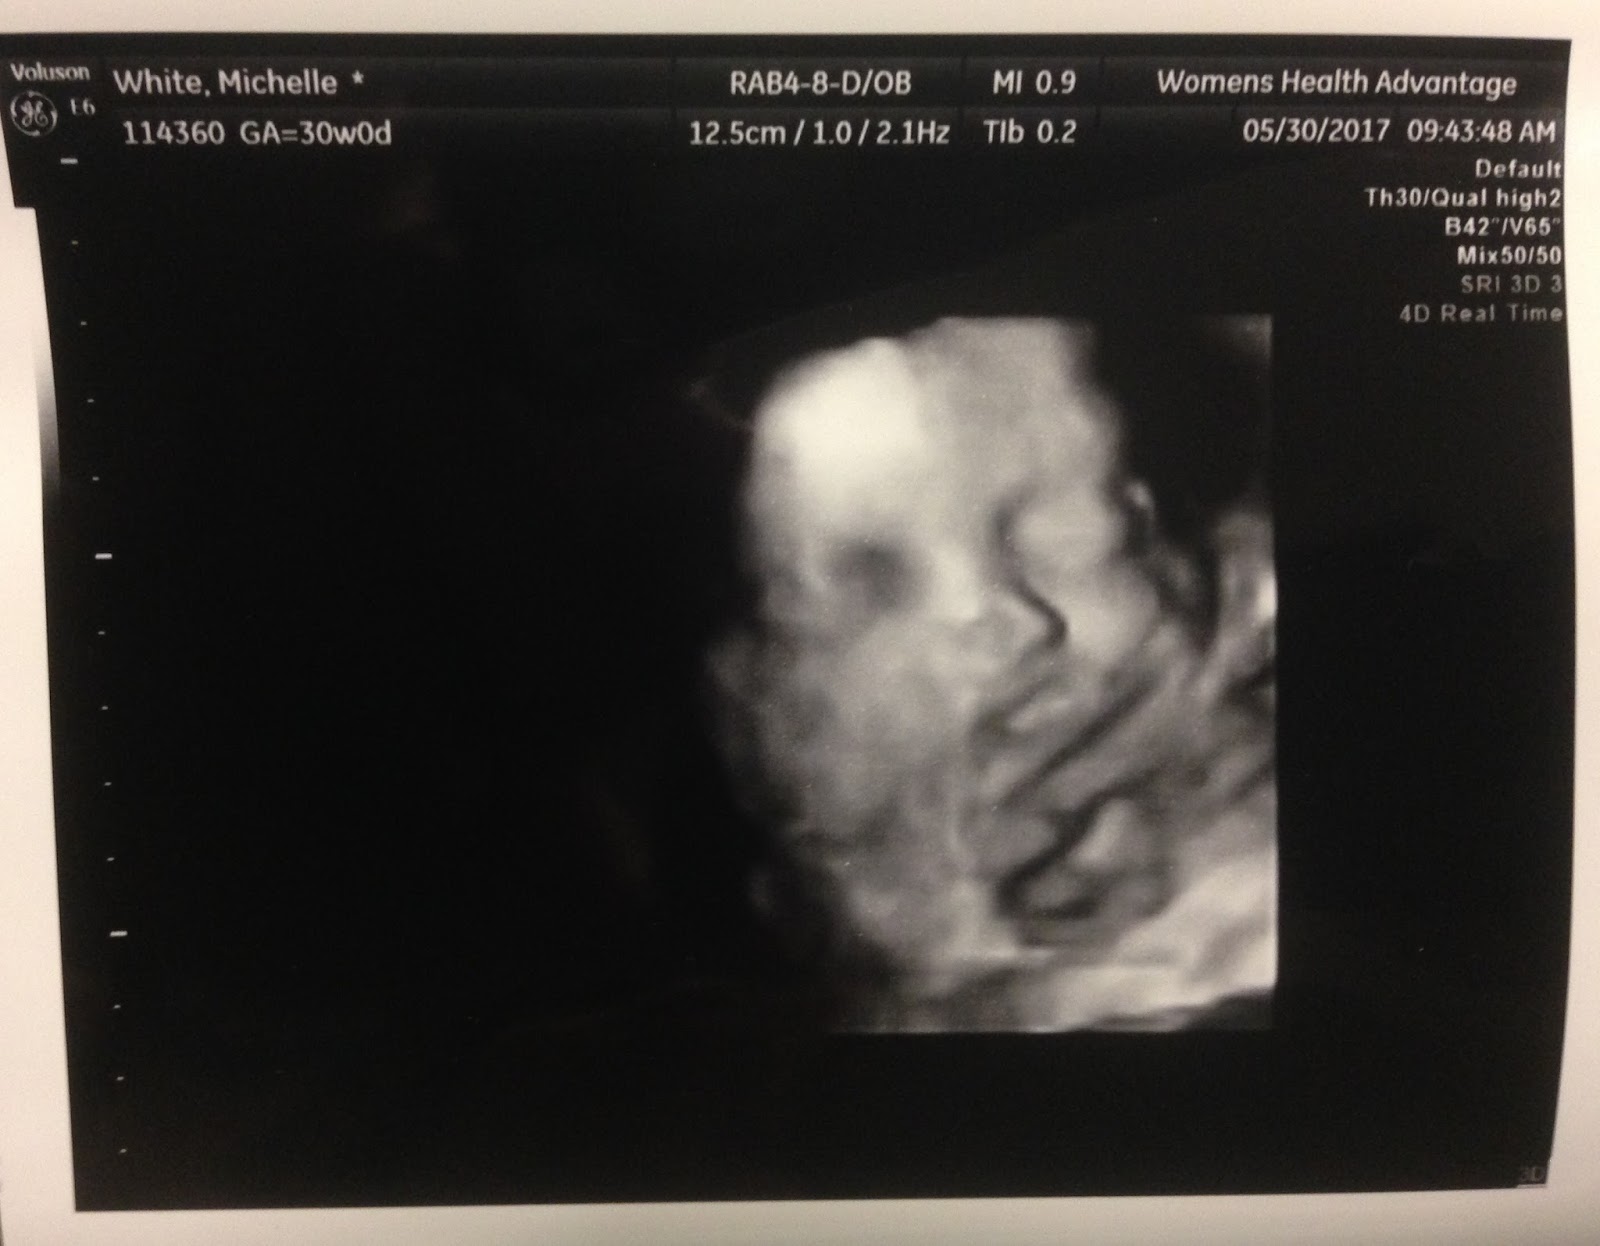

Sonogram Clinic 3d 4d Ultrasound Centers In Indiana Usa